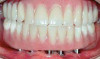

(9.) Branemark “High water” design.

Figure 9

(10.) Branemark “High water” design.

Figure 10

Many factors should be considered when designing implant-supported restorations to reduce the risk of peri-implantitis affecting physical removal of bacterial plaque at the FMG. Included are oral hygiene devices, accessibility, prosthetic shapes, and patient ability to comply with oral hygiene procedures. The design should be conveniently hygienic so patients can easily comply with the recommended oral hygiene procedures. Physical removal of bacterial plaque on the intaglio surface at and above the FMG reduces the risk of peri-implantitis in the sub-gingival transmucosal tissue around dental implants. The original fixed prosthetic design presented by Branemark, a "High water design", provided access to all surfaces for oral hygiene management without a patient complaint of food accumulation (Figure 9 and Figure 10). Notably, relief above the gingiva was not patient complaint with this design. Lack of embrasure access to the FMG and intaglio surfaces for oral hygiene management can lead to peri-implantitis (Figure 11 and Figure 12). Stein recommended a convex modified ridgelap pontic design with lingual and palatal access to facilitate plaque removal from the intaglio surface under pontics in fixed prosthetics with dental floss.20 These shapes should be standard for fixed implant-supported restorations whether individual or multi-unit restorations made of ceramo-metal or milled zirconia (Figure 13 through Figure 16).